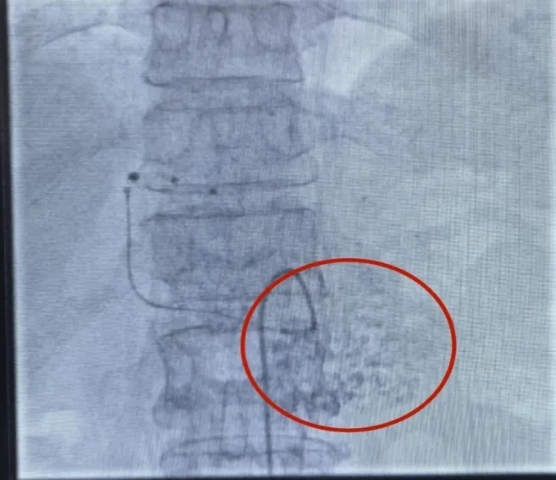

肝动脉化疗栓塞术(TACE)是一种通过动脉内注射抗癌药物联合栓塞剂的微创治疗手段,常用于治疗肝癌及转移性肝肿瘤。针对患者肝脏多发病变的情况,可采用DSA(数字减影血管造影)引导下的精准治疗方式进行手术。术中,通过局部麻醉穿刺股动脉置入导管,导管末端精确送达肝总动脉,在高压注射器造影下明确肝左叶病灶供血动脉走行,随后将微导管插入肝左动脉,缓慢注入含碘化油的乳化剂,精准封堵病灶供血。术中监测和术后影像均显示碘化油在肝左叶病灶内明显沉积,药物滞留效果良好。为确保疗效、减少副作用,手术采取多次缓慢灌注技术,最终精准阻断肿瘤供血,达到消解病灶的目的。术后,患者恢复良好,未出现明显并发症,目前正在制定后续治疗计划。

微导管超选至肝左动脉可见碘化油栓塞剂沉积于肿瘤组织。